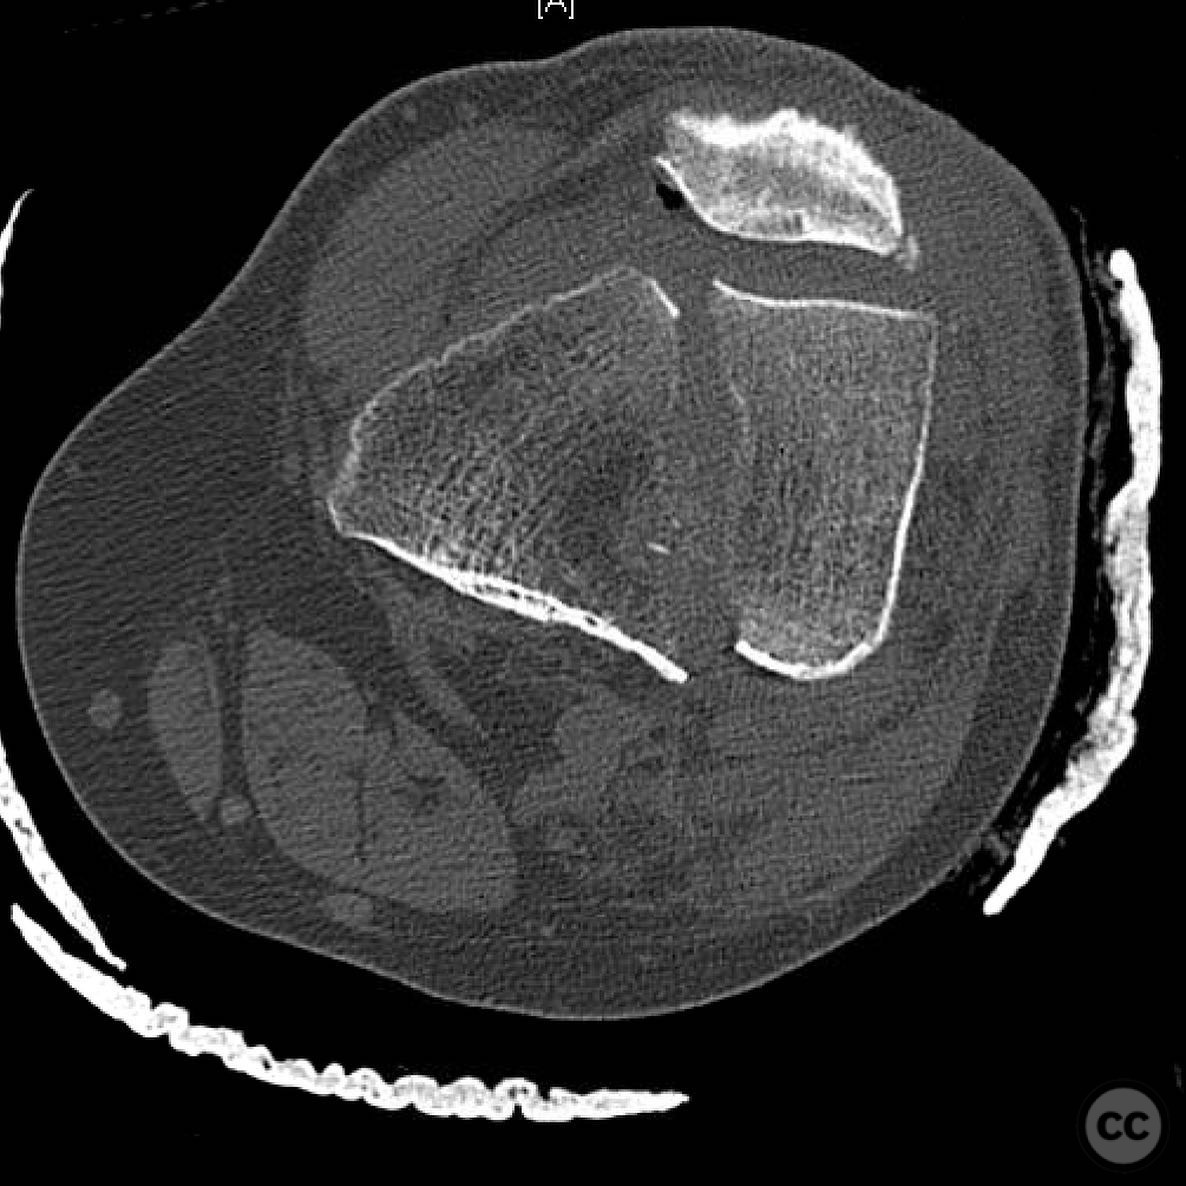

Clinical and radiological findings:  A 44-year-old male cyclist was involved in a collision with a car, resulting in open fractures of the distal femur and segmental tibia. The femoral fracture presented with a 4 cm transverse wound on the anterior aspect, while the tibial fracture had a 2 cm anterolateral wound at the distal site. There were no associated head, chest, or abdominal injuries, and compartment syndrome was not present. Vascular examination was unremarkable.

Planning remarks:  The preoperative plan involved initial debridement and irrigation of both open fractures. The tibia was prioritized for intramedullary nailing, followed by spanning external fixation of the distal femur. Definitive fixation of the distal femur was planned for two days post-initial stabilization.

Anatomical surgical approach:  For the tibia, a longitudinal incision was made to access the proximal tibial start site for intramedullary nailing. Percutaneous clamps were utilized for reduction, supplemented by blocking screws as needed. For the distal femur, an external fixator was applied initially, followed by an in situ lateral approach for plating after reduction was achieved.

The tibial nailing required precise identification of the start site under fluoroscopic guidance, with percutaneous clamps aiding in reduction. Blocking screws were considered but not necessary due to successful reduction with clamps alone. The distal femur presented challenges in achieving coronal and sagittal alignment, necessitating reliance on the external fixator for reduction before proceeding with plating.